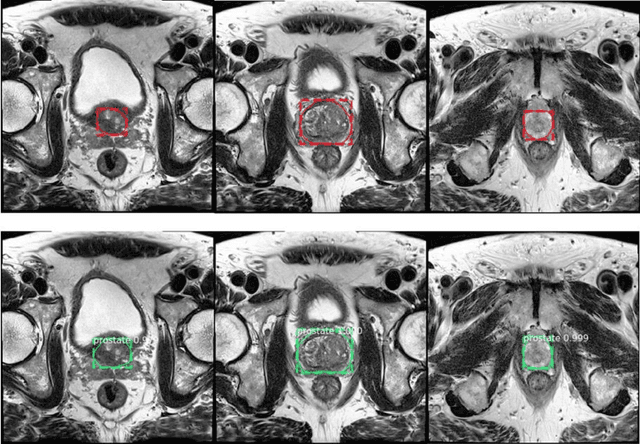

Abstract:Purpose: We aimed to develop deep machine learning (DL) models to improve the detection and segmentation of intraprostatic lesions (IL) on bp-MRI by using whole amount prostatectomy specimen-based delineations. We also aimed to investigate whether transfer learning and self-training would improve results with small amount labelled data. Methods: 158 patients had suspicious lesions delineated on MRI based on bp-MRI, 64 patients had ILs delineated on MRI based on whole mount prostatectomy specimen sections, 40 patients were unlabelled. A non-local Mask R-CNN was proposed to improve the segmentation accuracy. Transfer learning was investigated by fine-tuning a model trained using MRI-based delineations with prostatectomy-based delineations. Two label selection strategies were investigated in self-training. The performance of models was evaluated by 3D detection rate, dice similarity coefficient (DSC), 95 percentile Hausdrauff (95 HD, mm) and true positive ratio (TPR). Results: With prostatectomy-based delineations, the non-local Mask R-CNN with fine-tuning and self-training significantly improved all evaluation metrics. For the model with the highest detection rate and DSC, 80.5% (33/41) of lesions in all Gleason Grade Groups (GGG) were detected with DSC of 0.548[0.165], 95 HD of 5.72[3.17] and TPR of 0.613[0.193]. Among them, 94.7% (18/19) of lesions with GGG > 2 were detected with DSC of 0.604[0.135], 95 HD of 6.26[3.44] and TPR of 0.580[0.190]. Conclusion: DL models can achieve high prostate cancer detection and segmentation accuracy on bp-MRI based on annotations from histologic images. To further improve the performance, more data with annotations of both MRI and whole amount prostatectomy specimens are required.

Abstract:Prostate cancer (PCa) is the most common cancer in men in the United States. Multiparametic magnetic resonance imaging (mp-MRI) has been explored by many researchers to targeted prostate biopsies and radiation therapy. However, assessment on mp-MRI can be subjective, development of computer-aided diagnosis systems to automatically delineate the prostate gland and the intraprostratic lesions (ILs) becomes important to facilitate with radiologists in clinical practice. In this paper, we first study the implementation of the Mask-RCNN model to segment the prostate and ILs. We trained and evaluated models on 120 patients from two different cohorts of patients. We also used 2D U-Net and 3D U-Net as benchmarks to segment the prostate and compared the model's performance. The contour variability of ILs using the algorithm was also benchmarked against the interobserver variability between two different radiation oncologists on 19 patients. Our results indicate that the Mask-RCNN model is able to reach state-of-art performance in the prostate segmentation and outperforms several competitive baselines in ILs segmentation.